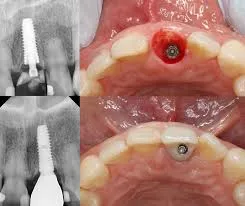

ایمپلنت فوری یا Immediate Implant به روشی گفته میشود که در آن پایه ایمپلنت بلافاصله پس از کشیدن دندان در همان جلسه در استخوان فک قرار داده میشود و در برخی موارد، روکش موقت نیز همان روز روی آن نصب میگردد.

مرحله سوم: کاشت پایه ایمپلنت

ایمپلنت در همان حفره دندان کشیدهشده قرار میگیرد.

مرحله چهارم: نصب روکش موقت

در صورت پایداری اولیه مناسب، روکش موقت بدون فشار اکلوزالی نصب میشود.